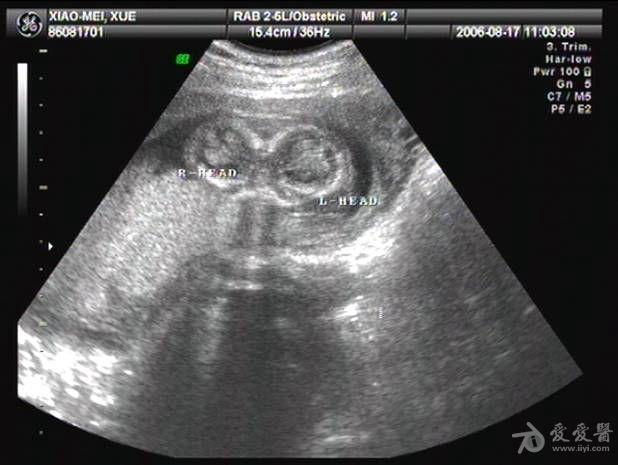

双胎超声图片

双胎超声图片,双胎图片

4例联体双胎图像及产后随访图片 超声医学讨论版 爱爱医医学论坛

准妈妈可知 双胞胎四维彩超检查好处

双胎妊娠